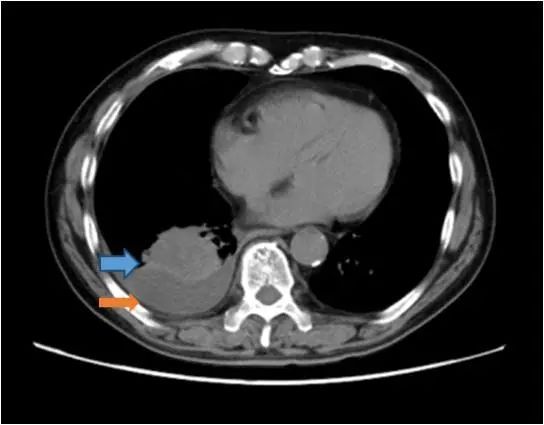

患者本次入院CT检查示右肺下叶恶性肿瘤(蓝色箭头),较2022年3月略增大;右侧胸腔积液(橙色箭头)。